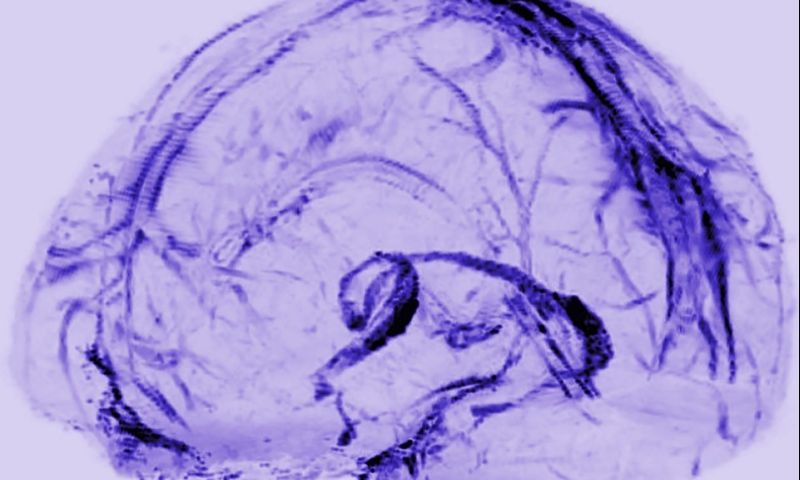

© Daniel Reich / National Institute of Neurological Disorders and Stroke